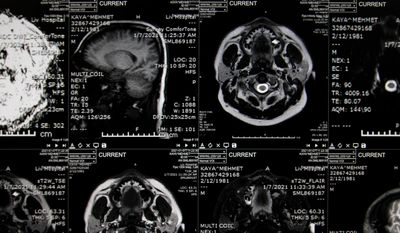

AG Neurocity, Batala, is equipped with modern infrastructure and a dedicated trauma care unit to manage a wide range of injuries — from minor head trauma to life-threatening neurological emergencies.

Dr. Atul Goel, Consultant Neurologist (MD, DM Neurology), plays a pivotal role in the care of trauma patients, especially those with neurological complications.